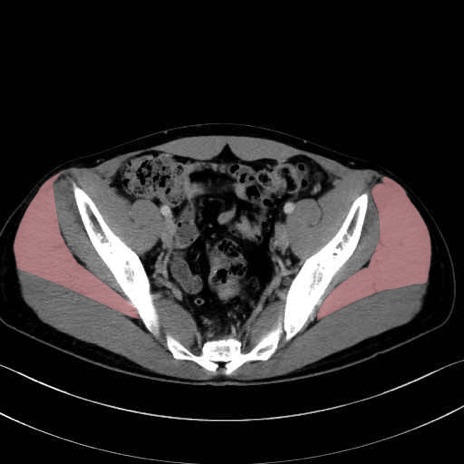

3. 殿部の筋肉(表層・中層・深層)

大殿筋 (Gluteus maximus)

中殿筋 (Gluteus medius)

小殿筋 (Gluteus minimus)